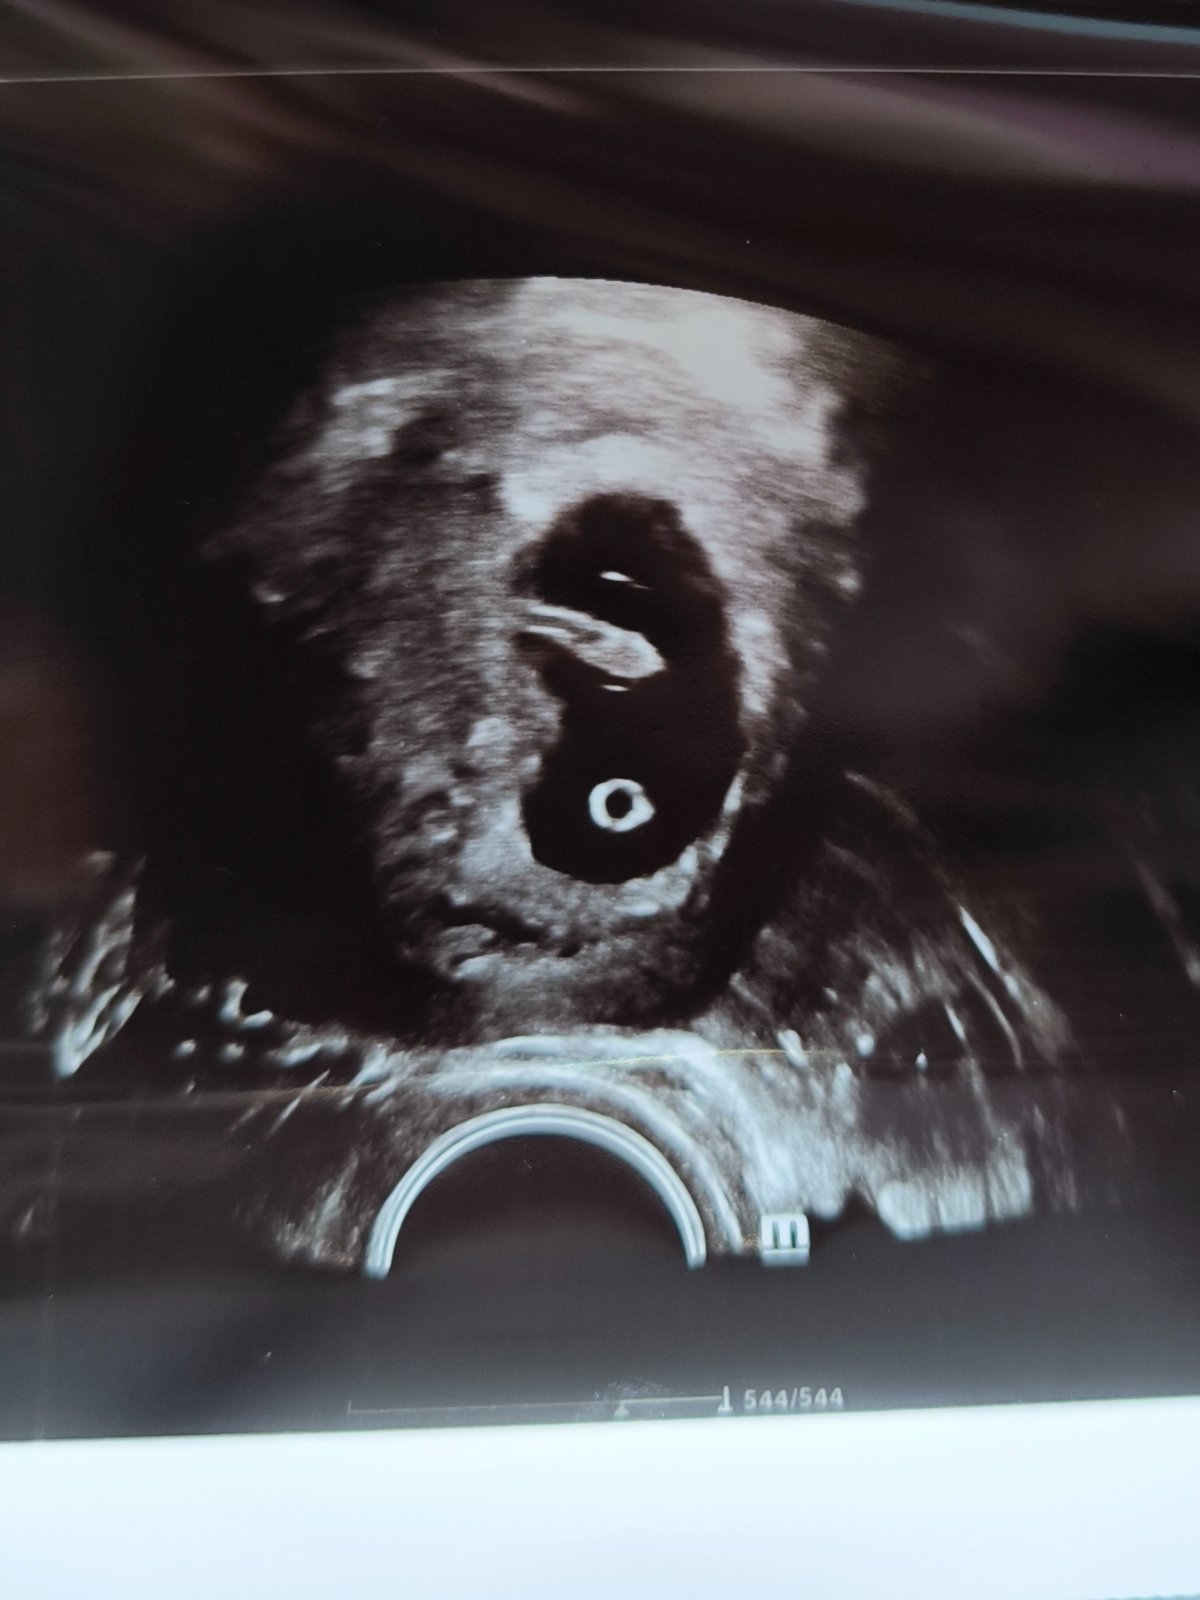

Sono v 8. týždni

Ahojte, včera som bola na sone, doktorka mi povedala že ie všetko ok, len ma zaujíma keď som si doma pozerala fotku, že čo to je za zhluk buniek naľavo pod embryom na tej fotke. Môze to byť vyvíjajúca sa placenta? Ak je tu niekto kto sa v tom vyzná, že by mi povedal čo to je.

@nikus_259 to je zltkovy vak a on sa neskôr zmení na placentu

@natalis1998 áno, tá gulička dole je žĺtkový vak, ale naľavo nad tou guličkou je čo? Myslím ako y na stene toho gestačn3ho valu, pod embryom